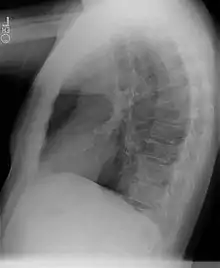

La tomodensitométrie thoracique, avec injection de produit de contraste iodé, permet généralement d'évoquer le diagnostic.